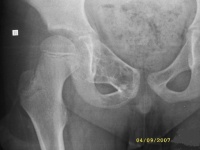

常发生于5到15岁的儿童,男性发病多于女性,比率约为2:1。病变部位多在长骨的干骺端。最常见部位为肱骨近端,其次为股骨近端。活动性(active相对具有侵袭性的)骨囊肿靠近骨骺区,随着儿童年龄增大,病灶会逐渐远离骨骺,成为非活动性(inactive)。在年龄超过17岁的患者,病变会在非长管骨发生,如跟骨、骨盆等。

有经验的骨肿瘤医生仅凭X线平片就可以作出骨囊肿的临床诊断。病变灶为边界清晰的液性低密度灶,四壁为薄层的硬化灶壳。病变灶略向近骨骺的干骺部位扩大。病灶非偏心性,也不破坏骨外壳,更不会突破骨质形成骨膜外反应骨,除非是在病理骨折后的愈合期。有时脱落的骨皮质成份落入囊腔中,X片显示被称为“落叶征”(FallenleaforFallenfragment)。当病灶发生在骨盆,CT扫描对病灶部位及囊肿形态的判断有价值。MRI可以明确囊内富含的液性成分。骨ECT扫描表现为外周薄的浓集而中央病灶冷区。

1.好发于4-20岁,多见于5-15岁儿童,少见于成人。好发于股骨颈、股骨上端和肱骨上端。随着年龄增长,囊肿逐渐向骨干方向移动。

3.X线摄片显示长骨干腄端或骨干部位有椭圆形溶骨破坏,边界清楚,其周围可见薄层硬化带,骨皮质可有轻度膨胀变薄。

3.X线摄片显示长骨干骺端有椭圆形密度均匀的透明阴影,病变局限,与

正常骨质间有明显界线,骨皮质膨胀变薄。

X线表现病损为界限清楚的射线透亮区,外有一薄层骨硬化边缘,由于囊肿膨胀性生长,造成骨皮质不规则变薄,X线片常呈假分叶状表现,尤多做囊肿在肱骨或股骨的干骺端向下扩展至骨干,向上扩展虽接近骨骺,但后者可被累及,病理性骨折很常见,囊肿可有骨嵴假象,病理检查见病损为单房的囊腔,其中充满清液,囊内衬以薄层纤维组织,骨折后腔内含血性液体并出现骨痂。

X线平片位于长骨干骺端,呈圆形、卵圆形或柱形,沿长骨纵轴发展,表现为轻度膨胀性生长,局部骨皮质变薄,边缘光整,无骨膜增生。合并病理骨折时,骨碎片向囊内移位,称“碎片陷落征”,有助于鉴别。

临床资料A组是待病理性骨折愈合后再治疗骨囊肿,共48例,年龄为6-43岁间;男39例,女9例。肱骨上端20例,肱骨中段6例,股骨上端9例其中(5例髋内翻),远端3例,股骨

颈2例,桡骨远端2例,尺骨远端1例,胫骨上端4例,腓骨头1例。B组是囊肿及骨折一并治疗,共6例,男5例,女1例。肱骨3例,股骨上端1例,股骨颈2例。

主要通过X线片及病理来诊断。X线片示,多发生于长管状骨的干骺端,髓腔中心呈圆形或卵圆形的透光区,边缘清晰而硬化,长轴与骨的长轴一致,多呈中心性生长,无骨膜反应,可见一锐利透光线横过骨病损区。病理:囊内可有少量黄色或血性稀薄液体,囊肿壁内衬一薄层纤维组织,囊内可有骨嵴分隔。镜下见囊壁由成纤维细胞、多核细胞和胶原纤维构成。